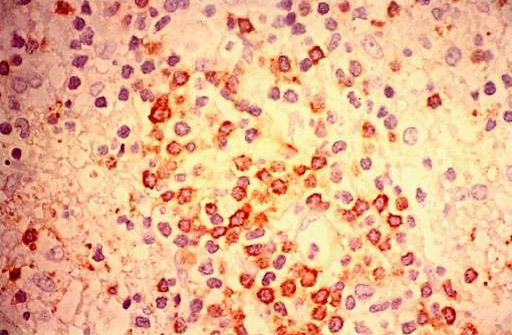

1.细菌感染:多来源于胃肠道的感染或其他器官经全身血液循环的感染。

2.病毒感染:多为上呼吸道感染或腮腺炎等所致。

3.结核菌感染:腹膜后淋巴结炎结核性者较为常见,可以是原发于腹膜后淋巴结,或继发于胃肠道、腹腔及肺部的结核病。